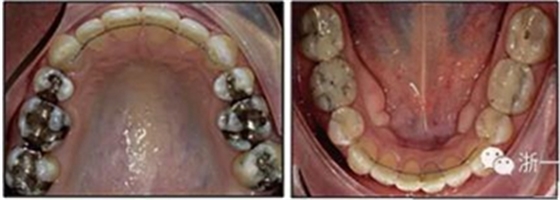

患者曾行正畸治療,現(xiàn)覺笑容不美觀前來就診。患者正面觀及側(cè)貌示下頜發(fā)育不足,偏高角,唇閉合不全。上下頜中線齊。覆合、覆蓋4毫米。磨牙關(guān)系及尖牙關(guān)系II類。上頜擁擠度4mm,下頜擁擠度6mm。4顆第一前磨牙在第一次正畸治療時已拔除。上下牙弓呈尖圓型,牙弓狹窄。

患者側(cè)貌改善,下唇唇肌緊張消失,上下唇可自然閉合。磨牙及尖牙關(guān)系糾正至I類,覆合覆蓋正常。上下頜弓型糾正至卵圓形,牙弓寬度增加。頭影測量分析示SNA角81.8°,ANB角3°。頭影測量重疊圖示下頜骨向后旋轉(zhuǎn),垂直面高度略有增加。